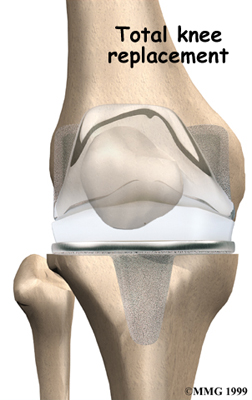

Artificial Knee Replacement

An artificial knee replacement is the ultimate solution for advanced knee OA.

Surgeons prefer not to put a new knee joint in patients younger than 60. This is because younger patients are generally more active and might put too much stress on the joint, causing it to loosen or even crack. A revision surgery to replace a damaged prosthesis is harder to do, has more possible complications, and is usually less successful than a first-time joint replacement surgery.

Related Document: FYZICAL St. George's Guide to Artificial Joint Replacement of the Knee